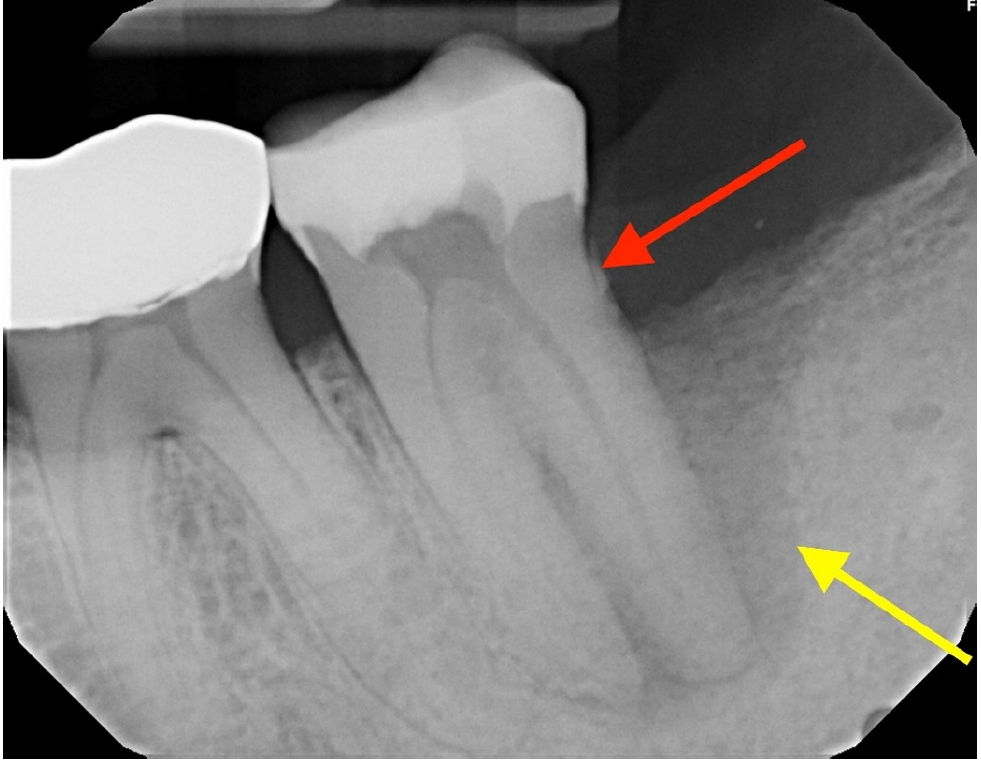

Radiographically, a “J-shaped” lesion was observed along the distal root of #18 (Figure 1), suggestive of a primary endodontic lesion with secondary periodontal involvement. A radiopaque fragment, consistent with a cemental tear, was identified along the distal root surface (Figure 1).

Differentiating cemental tears from other endodontic or periodontal pathologies requires a combination of clinical, radiographic, and histologic evaluations. Clinically, cemental tears present as isolated deep periodontal pockets, persistent inflammation despite treatment, and mobility in affected teeth [2,7,9]. Radiographically, a radiopaque fragment adjacent to the root surface, particularly in cases with rapid localized periodontal destruction, should raise suspicion [9]. Cone-beam computed tomography can enhance diagnostic accuracy, providing detailed three-dimensional imaging of root surfaces and periodontal defects [10]. In the present case, the presence of a “J-shaped” radiolucency along the distal root and a small radiopaque fragment was suggestive of a cemental tear contributing to the persistent periodontal involvement.

Figure 1.

“J-shaped” lesion observed along the distal root of #18 (yellow arrow). A radiopaque fragment, consistent with a cemental tear, was identified along the distal root surface (red arrow).